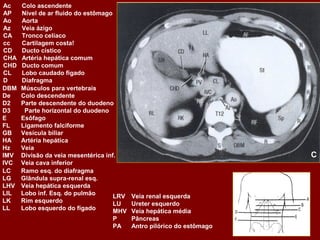

Ac Colo ascendente AP Nível de ar fluido do estômago Ao Aorta Az Veia ázigo CA Tronco celíaco cc Cartilagem costa! CD Dueto cístico CHA Artéria hepática comum CHD Dueto comum CL Lobo caudado fígado D Diafragma DBM Músculos profundos do De Colo descendente D2 Parte descendente do duodeno D3 Parte horizontal do duodeno E Esôfago FL Ligamento falciforme GB Vesícula biliar HA Artéria hepática Hz Veia IMV Divisão da veia mesentérica inf. A IVC Veia cava inferior LC Ramo esq. do diafragma LG Glândula supra-renal esq. LHV Veia hepática esquerda LIL Lobo inf. Esq. do pulmão LRV Veia renal esquerda LK Rim esquerdo LU Ureter esquerdo LL Lobo esquerdo do fígado MHV Veia hepática média P Pâncreas PA Antro pilórico do estômago

Ac Colo ascendente AP Nível de ar fluido do estômago Ao Aorta Az Veia ázigo CA Tronco celíaco cc Cartilagem costa! CD Dueto cístico CHA Artéria hepática comum CHD Dueto comum CL Lobo caudado fígado D Diafragma DBM Músculos profundos do De Colo descendente D2 Parte descendente do duodeno D3 Parte horizontal do duodeno E Esôfago FL Ligamento falciforme GB Vesícula biliar HA Artéria hepática Hz Veia IMV Divisão da veia mesentérica inf. IVC Veia cava inferior B LC Ramo esq. do diafragma LG Glândula supra-renal esq. LHV Veia hepática esquerda LIL Lobo inf. Esq. do pulmão LRV Veia renal esquerda LK Rim esquerdo LU Ureter esquerdo LL Lobo esquerdo do fígado MHV Veia hepática média P Pâncreas PA Antro pilórico do estômago

Ac Colo ascendente AP Nível de ar fluido do estômago Ao Aorta Az Veia ázigo CA Tronco celíaco cc Cartilagem costa! CD Ducto cístico CHA Artéria hepática comum CHD Ducto comum CL Lobo caudado fígado D Diafragma DBM Músculos para vertebrais De Colo descendente D2 Parte descendente do duodeno D3 Parte horizontal do duodeno E Esôfago FL Ligamento falciforme GB Vesícula biliar HA Artéria hepática Hz Veia IMV Divisão da veia mesentérica inf. C IVC Veia cava inferior LC Ramo esq. do diafragma LG Glândula supra-renal esq. LHV Veia hepática esquerda LIL Lobo inf. Esq. do pulmão LRV Veia renal esquerda LK Rim esquerdo LU Ureter esquerdo LL Lobo esquerdo do fígado MHV Veia hepática média P Pâncreas PA Antro pilórico do estômago

Ac Colo ascendente AP Nível de ar fluido do estômago Ao Aorta Az Veia ázigo CA Tronco celíaco cc Cartilagem costa! CD Dueto cístico CHA Artéria hepática comum CHD Dueto comum CL Lobo caudado fígado D Diafragma DBM Músculos profundos do De Colo descendente D2 Parte descendente do duodeno D3 Parte horizontal do duodeno E Esôfago FL Ligamento falciforme GB Vesícula biliar HA Artéria hepática Hz Veia IMV Divisão da veia mesentérica inf. D IVC Veia cava inferior LC Ramo esq. do diafragma LG Glândula supra-renal esq. LHV Veia hepática esquerda LIL Lobo inf. Esq. do pulmão LRV Veia renal esquerda LK Rim esquerdo LU Ureter esquerdo LL Lobo esquerdo do fígado MHV Veia hepática média P Pâncreas PA Antro pilórico do estômago